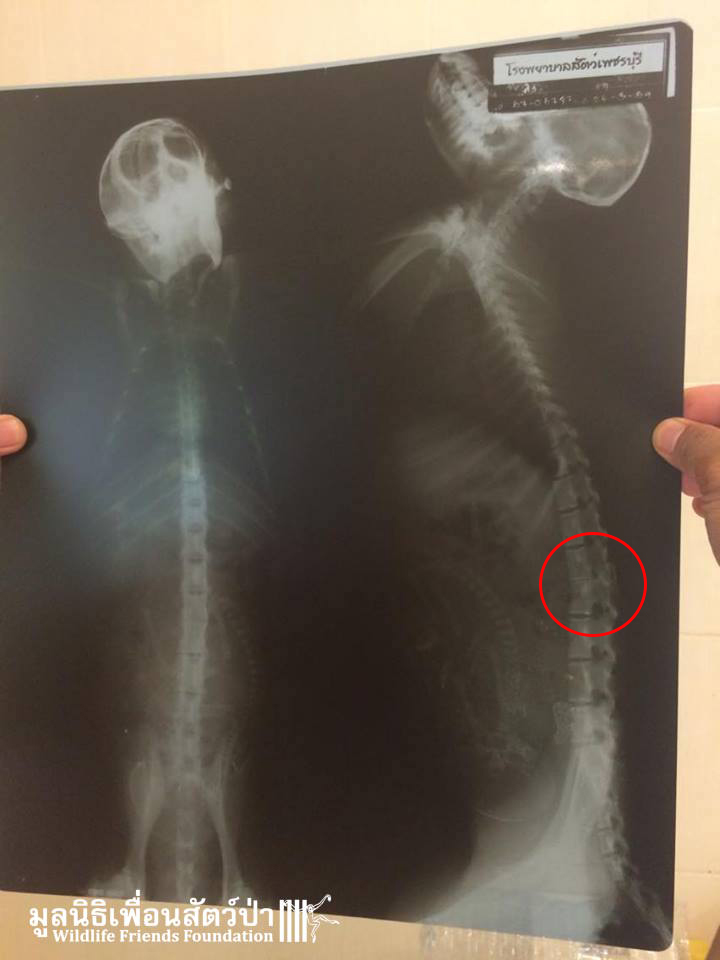

Yesterday we received a call about a seriously injured female long-tailed macaque (Macaca fascicularis) in a coastal area in Phetachburi. She had fallen from a tree into the muddy water under a mangrove forest in which she lives. A villager found her unable to breath with her face under the water and rescued her, he then took her home, washed and fed her then called us to help. Upon arrival it seems she has a deformed spine caused by an old injury and possibly some nerve damage. She was rushed to a local hospital for an x-ray; this confirmed the vet teams suspicion that she has a deformed spine, to our surprise the x-ray revealed that she is carrying a baby. She was then taken to the WFFT Wildlife Hospital for further treatment.

She is currently receiving round the clock intensive care at the WFFT Wildlife Hospital. She is eating and drinking well, and is able to grasp some things with her hands. Her future is currently uncertain but we will do everything in our power to try and save this special soul and her baby. We will keep you posted on her progress.